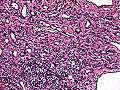

| Micrograph of a kaposiform hemangioendothelioma with "glomeruloid" nodules of endothelial cells. | |

- Kaposiform hemangioendothelioma (also known as "Infantile kaposiform hemangioendothelioma"[3]) is an uncommon vascular tumor, first described by Niedt, Greco, et al. (Hemangioma with Kaposi's sarcoma-like features: report of two cases.(Niedt GW, Greco MA, Wieczorek R, Blanc WA, Knowles DM 2nd. that affects infants and young children, with rare cases having also been reported in adults.Pediatr Pathol. 1989;9(5):567-75.)[2]:596[3]:1782